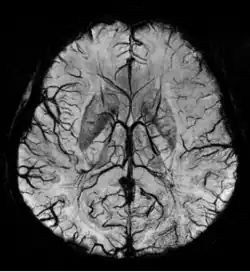

Gradient recalled echo (GRE) imaging is the conventional way to detect hemorrhage in CAA, however SWI is a much more sensitive technique that can reveal many micro-hemorrhages that are missed on GRE images.[7] A conventional gradient echo T2*-weighted image (left, TE=20 ms) shows some low-signal foci associated with CAA. On the other hand, an SWI image (center, with a resolution of 0.5 mm x 0.5 mm x 2.0 mm, projected over 8mm) shows many more associated low-signal foci. Phase images were used to enhance the effect of the local hemosiderin build-up. An example phase image (right) with yet higher resolution of 0.25 mm x 0.25 mm x 2.0 mm shows a clear ability to localize multiple CAA-associated foci.